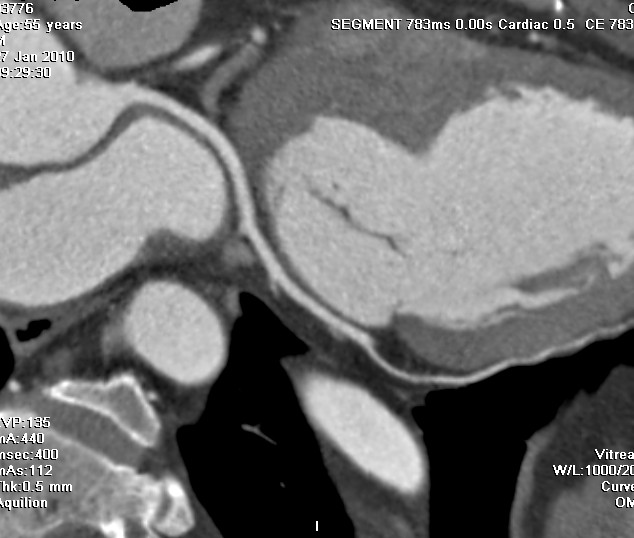

标题: CT24400:患者54岁,心前区不适进行心脏冠脉造影检查。 [打印本页]

标题: CT24400:患者54岁,心前区不适进行心脏冠脉造影检查。

患者54岁,心前区不适进行心脏冠脉造影检查。高手看看有问题没有?

图像很漂亮,好像未见异常